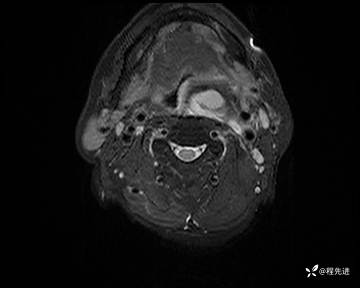

MRI平扫+增强:

T2压脂: